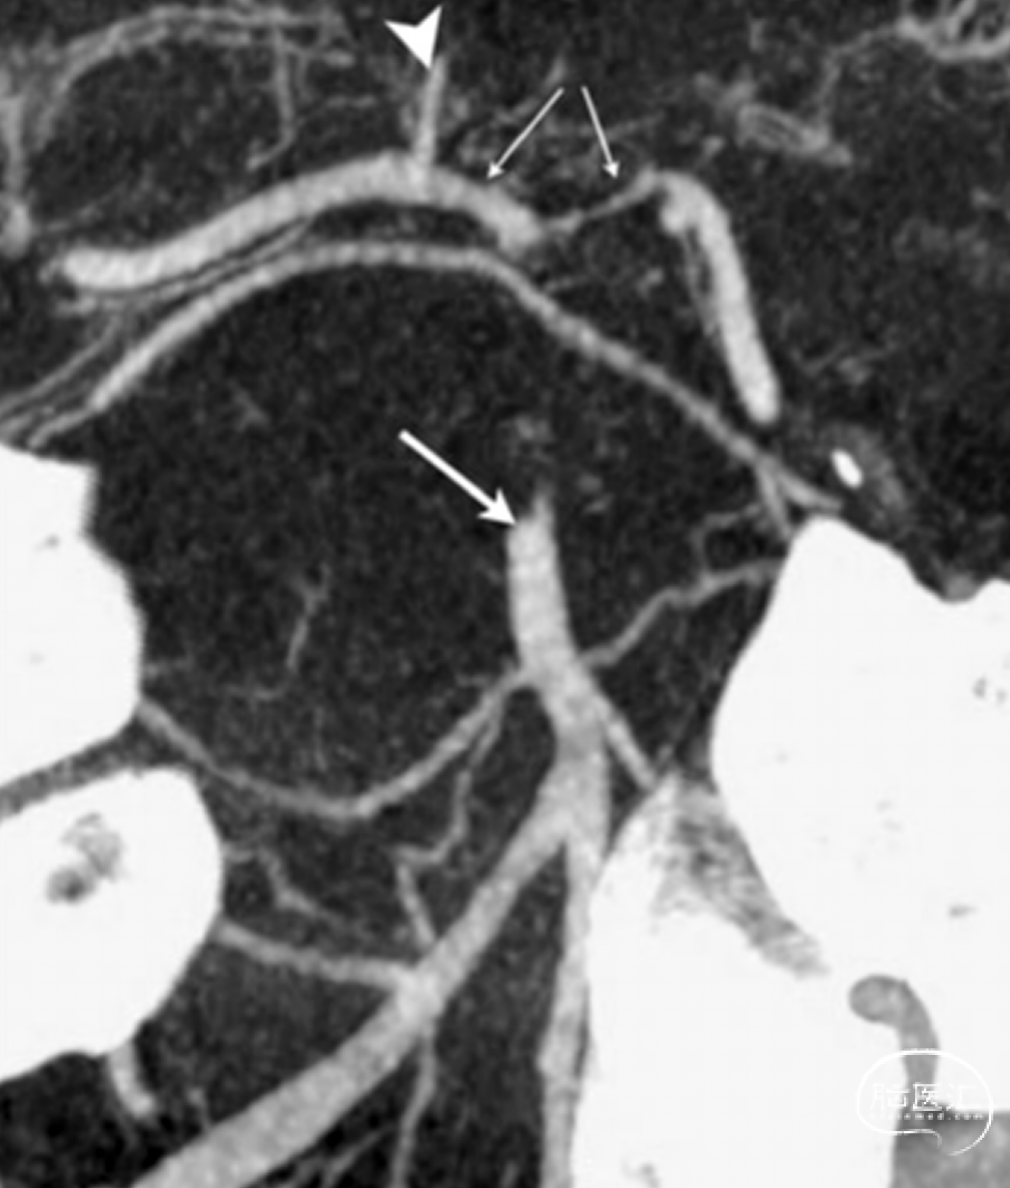

VasoCT提供业内最多620张采集影像达到超高分辨率显示颅内血管与支架形态,为介入医生打开高清的世界:

能够清晰显示颅内血管结构、支架形态及其与血管和弹簧圈的关系,助力医生精准评估支架展开和贴壁情况,及时调整偏差,提高患者预后;

去金属伪影,避免由于金属物(弹簧圈等)在医学影像中产生的伪影对图像质量的影响,从而提高诊断的准确性;

针对于缺血性卒中,可同时显示血栓近、远端血管,明确血栓的大小和范围;

应用静脉注射模式也可用于动脉瘤术后的复查,避免后期患者创伤以及多余X射线的伤害。

动脉VasoCT实现1毫米高清显示模式,任何耗材情况均可快速确认支架展开情况。

静脉注射模式下可实现卒中远端血管以及血栓位置的确定。

明确血栓位置、范围

CBCTA (27cm视野)